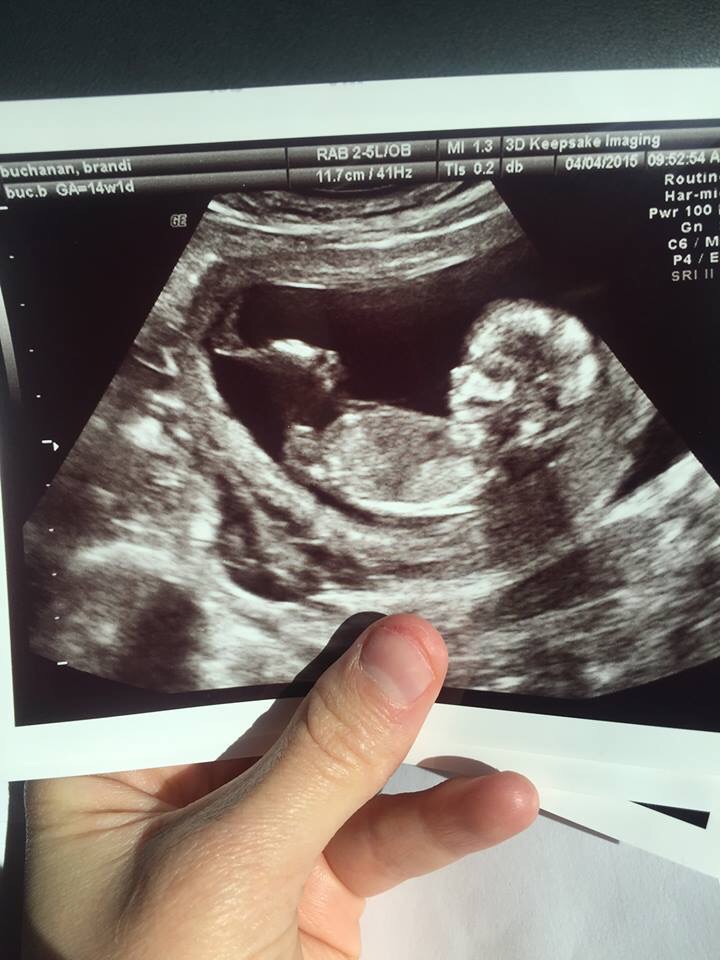

13 week 3d ultrasound gender accuracy. If you are experiencing a bit of gender disappointment have faith we confirmed our fourth child was a girl by ultrasound october 9 2014. We currently begin our ultrasound based gender determination ultrasound at 13 weeks and our determinations for that age have been accurate to date. Scan was at 19w 3d and i have about 45 potty shots which has no evidence of boy bitsnot sure if i should get rid of my boy things just yet. Can babys gender be determined with 3d4d ultrasounds.

How often is a 12 week gender ultrasound wrong. We can accurately determine gender after the 13 week mark 13 weeks 0 days 13 weeks 1 day perfect timing if the baby is in the optimal position rare that they dont cooperate at this visit and if the babys measurements agree with your due date. We can schedule you for a second appointment if these criteria are not met. If you enjoyed boy or girl ultrasound wrong.

Gender determination is successful in majority of cases but not in every case it is never 100 and can sometimes be inaccurate due to factors such as amniotic fluid levels babys positioning maternal weight and body type. Is the 12 ultrasound accurate for gender prediction. If you are 15 weeks 0 days or more then our pink or blue package is for you. From this week onwards your baby will grow rapidly and your doctor might suggest an ultrasound scan to check his progress.

After the 20 th week 3d ultrasounds are generally more accurate. An ultrasound scan in the 13 th week can tell you a lot about your babys health and is important.